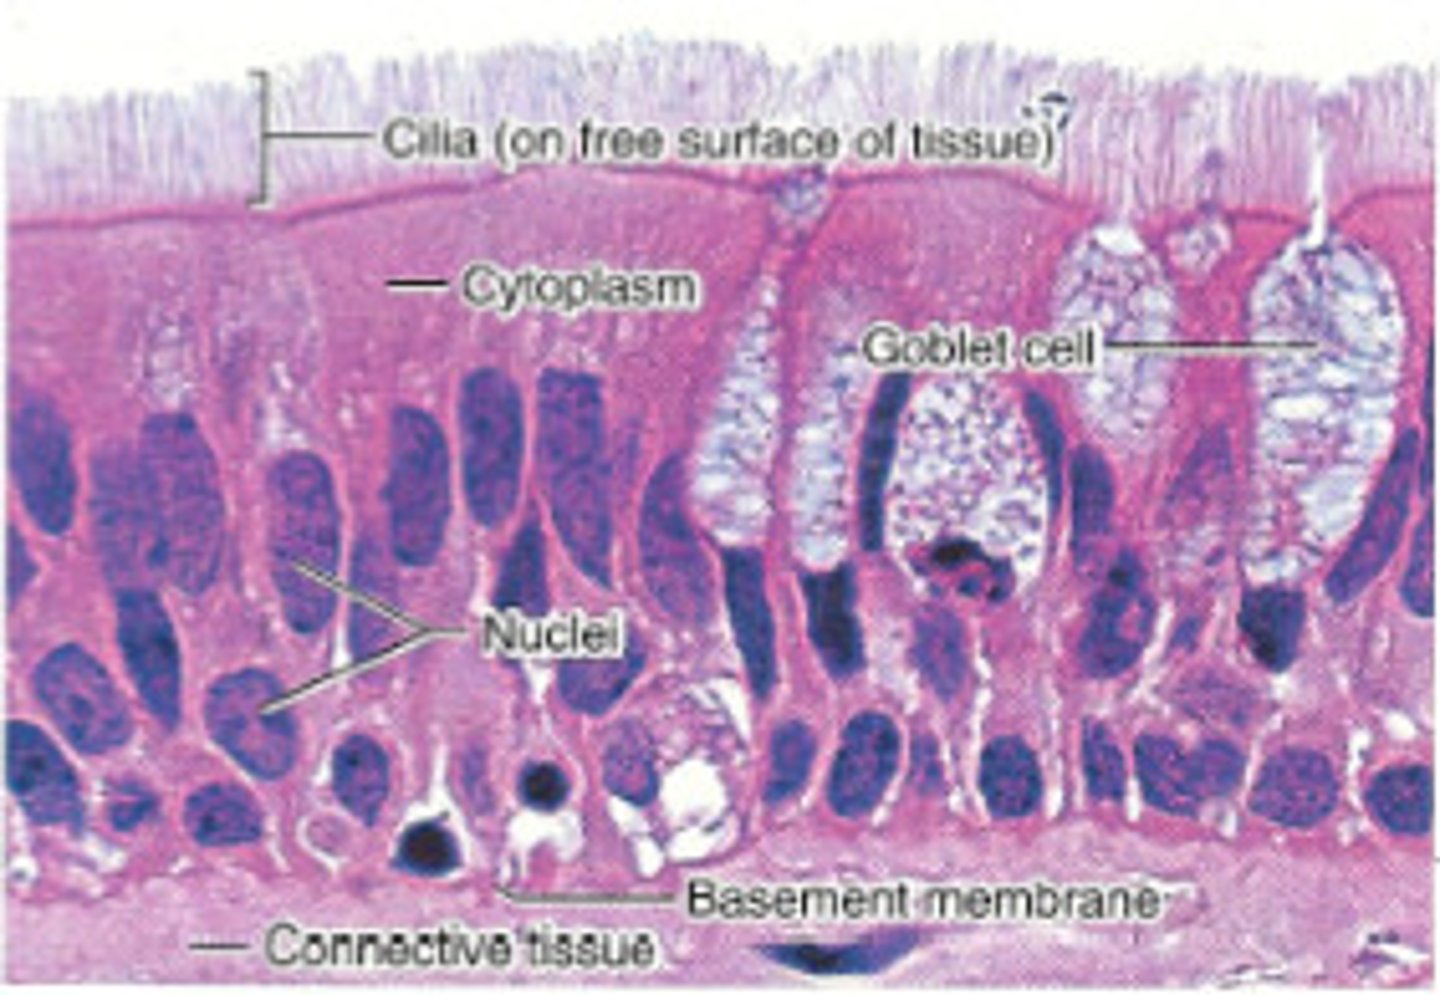

respiratory epithelium

ciliated lining of much of the conducting zone that is specialised to remove debris and pathogens, and produce mucus